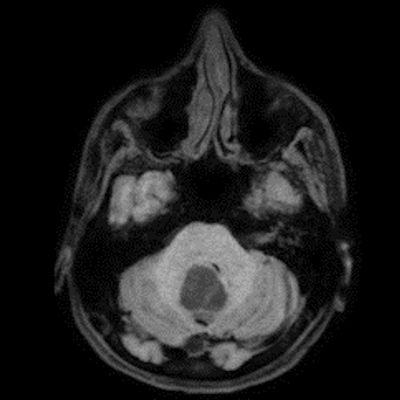

24 yaş, E

Baş ağrısı

4.ventrikül tabanına oturmuş posterior fossada hemanjioblastoma

bilateral vestibuler schwannoma ve kist duvarı kontrastlanmaması nedeniyle hemangioblastom ancak yeri itibariyle pilositik astrositom ayırıcı tanısı

Hemangioblastoma